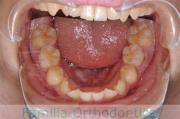

犬歯が八の字になっているので何とかしてほしいということで来院されました。上顎犬歯が左右とも前歯の方に向いていて、一期治療でまずは萌出誘導を行いました。

二期治療は、出っ歯の要素が強かったため、上顎のみ第二小臼歯を抜歯しています。

二期治療は2年強、25回程度の通院が必要でした。犬歯の埋伏歯は、うまく出すことができない場合があったり、出す際に周囲の歯の歯根に傷をつけるリスクがあったりします。